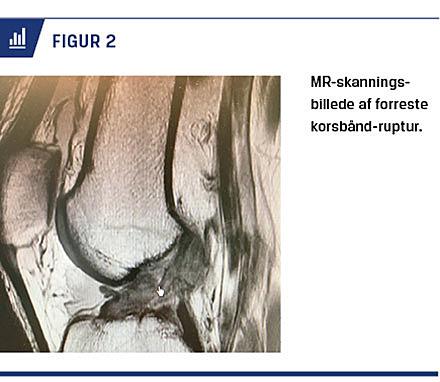

Objektivt finder man løshed ved Lachmans test og/eller skuffetest (Figur 1). Løsheden bør altid kvantificeres med en laksitetsmåler, f.eks. et Rolimeter (Figur 1). Klinisk undersøgelse af en totalruptur er lige så sensitiv og specifik som en MR-skan-ning [3] (Figur 2).

Ved en MR-skanning kan man påvise strukturelle forandringer ved korsbåndsskade og vise associerede skader (Figur 2). Man finder typisk bone bruise i den laterale femurkondyl og den laterale tibiakondyl. Bone bruise er en kompressionsskade af brusk og den underliggende knogle og er opstået ved kollision imellem de to knogler ved traumet. I mange tilfælde fremtræder ACL normalt ved en MR-skanning trods en komplet overrivning [2, 3].